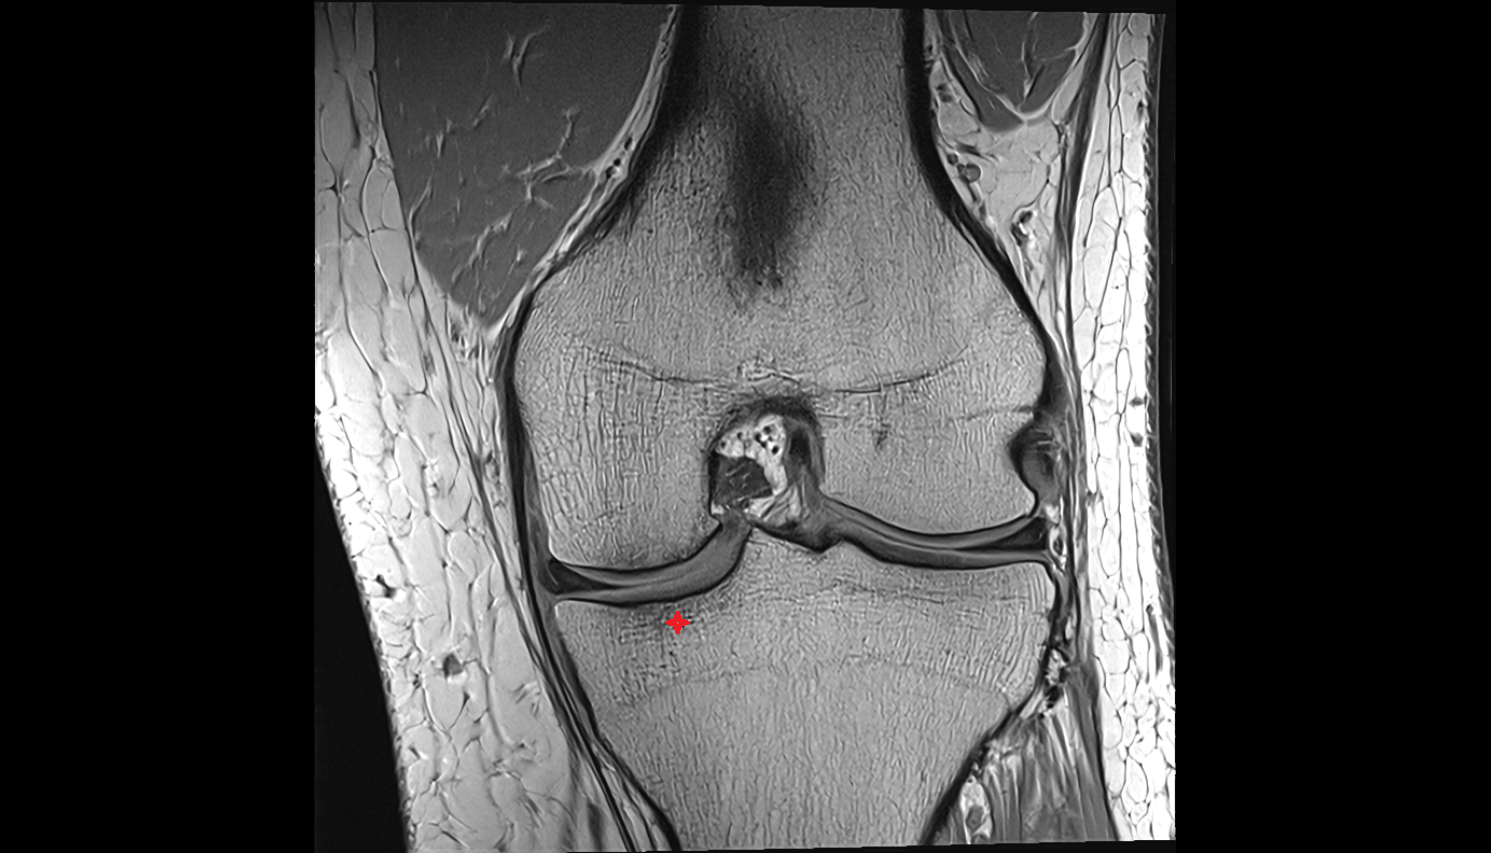

- Meniscus cartilage

- Medial meniscus

- Lateral meniscus

- Knee Joint

- Anterior cruciate ligament

- Posterior cruciate ligament